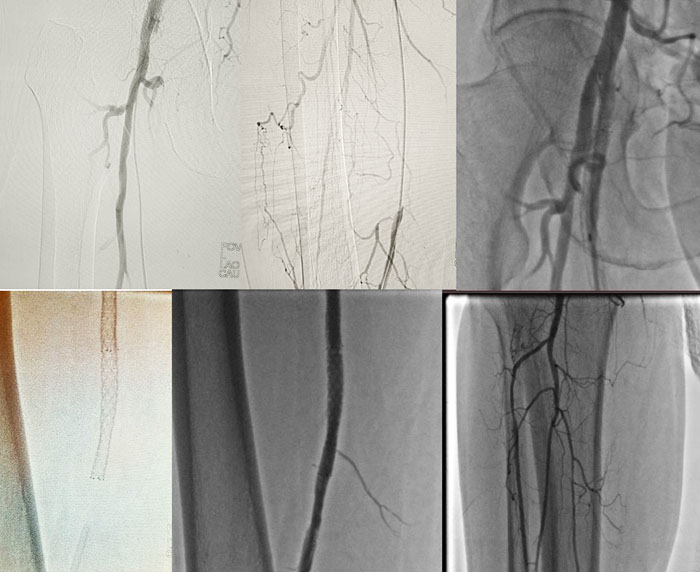

Результаты артериральных реконструкций

До и После